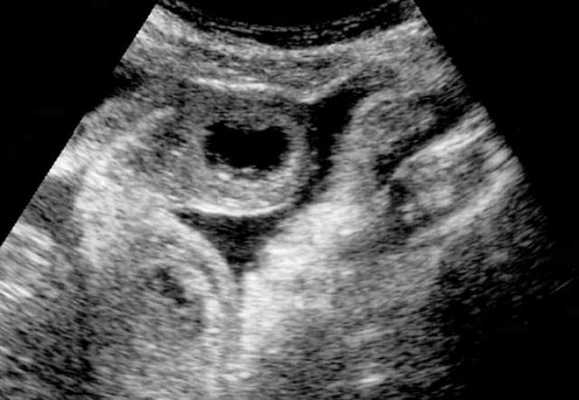

(а) При КТ с контрастированием в аксиальной проекции выявлена транспозиция верхней брыжеечной артерии (указатель) и вены (стрелка).

(б, в) На более низких уровнях при КТ в аксиальной проекции выявлен симптом «водоворота» (стрелка), представляющий собой перекручивание верхней брыжеечной вены и ее ветвей, брыжеечного жира и петель кишки вокруг верхней брыжеечной артерии по часовой стрелке.

Ультрасонография (УС) информативна при патологическом перекручивании верхних брыжеечных артерии и вены (симптом «водоворота»), выявляемом при цветном допплеровском картировании. Однако зависимость от мастерства исследователя, а также газ в тонкой кишке, мешающий исследованию верхних брыжеечных сосудов, часто ограничивают диагностическую пользу. КТ стала важным методом визуализационной диагностики, особенно при завороте тонкой кишки у взрослых. Как и при УС, характерным признаком при КТ служит симптом «водоворота», который возникает в результате перекручивания верхней брыжеечной вены и ее ветвей, брыжеечного жира, кишки и ветвей верхней брыжеечной артерии вокруг самой верхней брыжеечной артерии, чаще по часовой стрелке.

• Верхняя брыжеечная вена (ВБВ) занимает более вентральное положение либо находится слева от верхней брыжеечной артерии (ВБА):

о Заворот центральной части пищеварительной трубки характеризуется симптомом «водоворота» или «вихря», который формируется при скручивании брыжеечных сосудов и кишки